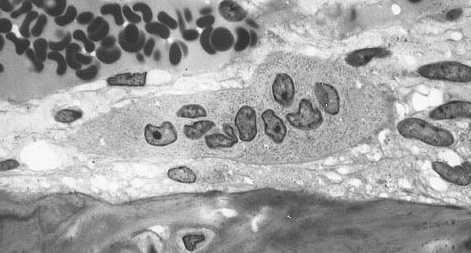

골격의 대사

뼈는 활발한 대사가 일어나는 조직. 새로운 뼈를 만드는 조골세포(osteoblast, bone forming cell)와 뼈를 파괴하는 파골세포(osteoclast, bone resorbing cell) 두가지 세포가 있음. 조골세포는 골수에서 생성되며 지속적으로 뼈의 표면에 단백질과 기질을 분비하고 이들 단백질과 기질로 구성된 기본 망상구조안에 무기질을 축적(석회화, mineralization)하여 새로운 뼈를 생성하는 세포임. 반면 파골세포는 이미 만들어진뼈의 무기질을 용해하고 단백질과 기질을 분해하여 골격의 재흡수(분해)를 담당하는 세포로 크기가 크며다핵세포임.

사춘기, 성인초기에는 조골세포의 작용이 우세하여 골질량이 증가, 30-35세에 최대에 달함.

40세까지 동적평형을 이루면서 골질량이 일정하게 유지

이후 파골세포의 활성이 커져 골손실이 발생.